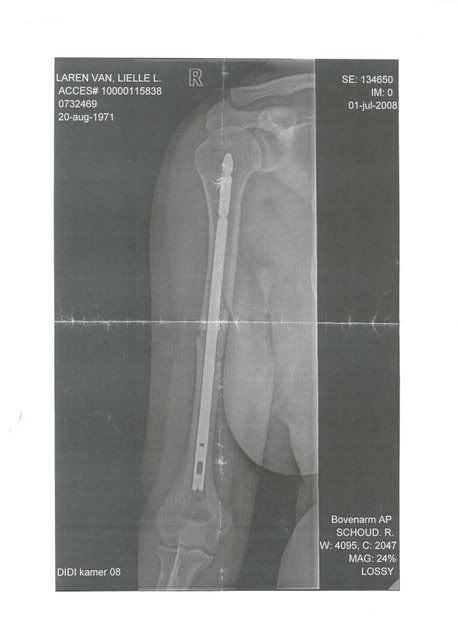

Na 3 uur op de eerste hulp te hebben gezeten mochten we eindelijk zo'n kamertje in, de dokter ging voelen en zei dat hij dacht aan een spierenkwestie maar helaas, na het zien van de foto kwam hij nogal gehaast terug en zei dat hij slecht nieuws had.

Mijn schouder is gebroken, net onder de schouderkop, volgens hem werd dit een vreselijk zwaar en pijnlijk proces.

Vandaag te horen gekregen dat ik niet geopereerd hoef te worden, volgende week dinsdag moet ik terugkomen voor foto's.